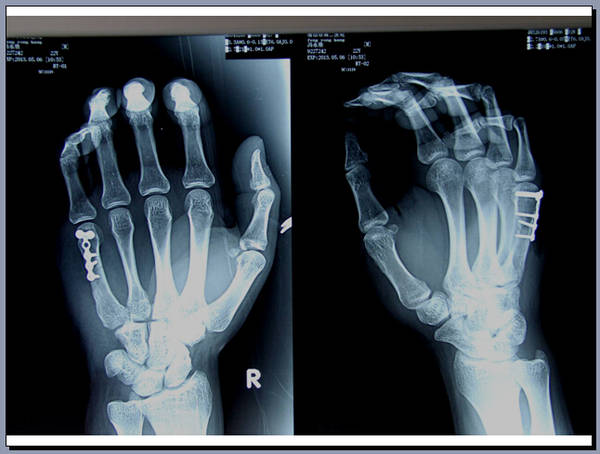

手外科会议带去一个讨论题目